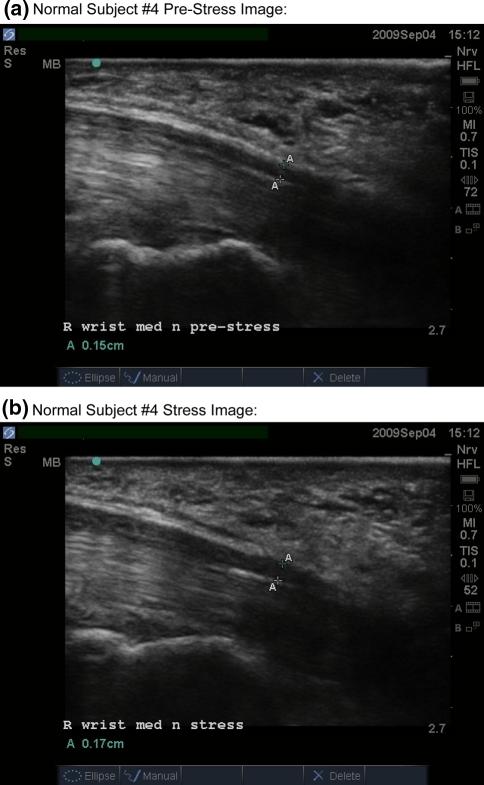

Median nerve (MN) compression is a recognized component of carpal tunnel syndrome (CTS). In order to document compressive changes in the MN during hand activity, the carpal tunnel was imaged with neuromuscular ultrasound (NMUS). Ten patients with CTS and five normal controls underwent NMUS of the MN at rest and during dynamic stress testing (DST). DST maneuvers involve sustained isometric flexion of the distal phalanges of the first three digits. During DST in the CTS patients, NMUS demonstrated MN compression between the contracting thenar muscles ventrally and the taut flexor tendons dorsally. The mean MN diameter decreased nearly 40%, with focal narrowing in the mid-distal carpal canal. Normal controls demonstrated no MN compression and a tendency towards MN enlargement, with an average diameter increase of 17%. Observing the pathologic mechanism of MN injury during common prehensile hand movements could help better understand how to treat and prevent CTS.

正中神经(MN)受压是腕管综合征(CTS)的一个公认组成部分。为了记录手部活动过程中 MN 的压迫变化,使用神经肌肉超声(NMUS)对腕管进行成像。10 名 CTS 患者和 5 名正常对照者在休息和动态应力测试(DST)期间接受 MN 的 NMUS 检查。DST 操作包括持续等距地弯曲第一到第三指的末节指骨。在 CTS 患者的 DST 过程中,NMUS 显示 MN 在收缩的鱼际肌肉下方和紧绷的屈肌腱上方受到压迫。MN 直径平均减小近 40%,在腕管中远段出现局灶性狭窄。正常对照者未出现 MN 受压,MN 直径有增大趋势,平均增加 17%。观察常见抓握手部运动过程中 MN 损伤的病理机制,有助于更好地理解如何治疗和预防 CTS。